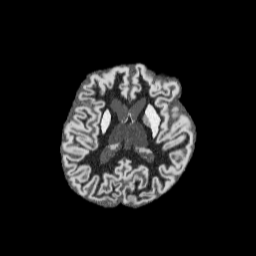

T1w(HF)T1w(LF)FLAIR(HF)Refer to captionRefer to captionRefer to captionRefer to captionRefer to captionRefer to captionRefer to captionRefer to captionRefer to captionRefer to captionRefer to captionRefer to captionRefer to captionRefer to captionRefer to captionInput(HF: high-field; LF: low-field)BrainFM featuresSCRATCH features

Figure 3: SCRATCH, well trained on high-field T1w scans with the same model architecture as BrainFM, produces highly descriptive features for high-field T1w images (1st1^{\text{st}} row), but does not preserve the same high quality useful for downstream tasks when handling low-field (2nd2^{\text{nd}} row) or other contrasts (3rd3^{\text{rd}} row).

We set the intra-subject samples within a mini-batch to have random contrasts and “mild-to-severe”, increasing level of corruptions (Fig. 2 (left)), to maximize the intra-subject variance while ensuring the stability of the training process against extreme corruption levels. As shown in Fig. 3, BrainFM obtains contrast/resolution-robustness that cannot be achieved by models trained from real images (due to the limited variability in their appearance), regardless of the backbone choices.